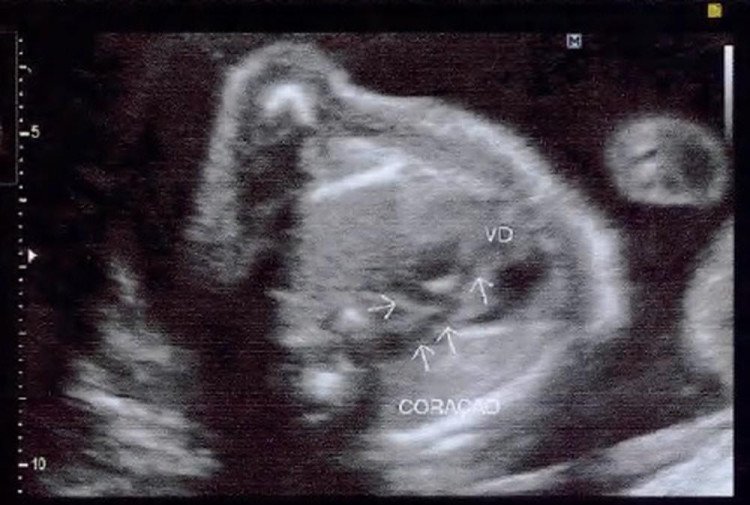

Uma jovem de 20 anos, que está no 38º mês de gestação, precisa ser levada com urgência para Curitiba ou São Paulo, para dar à luz em um hospital com equipe médica especializada em cirurgia cardíaca de alta complexidade em recém-nascidos.

Consta da ação que, quando estava com 24 semanas de gravidez, a jovem fez um exame morfológico em uma clínica em Cáceres, a 220 km de Cuiabá, o qual apontou que o bebê estava com malformação cardíaca. Logo depois, ainda no mês de agosto, ela procurou a Secretaria Municipal de Saúde de Porto Esperidião para pedir ajuda e então foi encaminhada ao Hospital Universitário Júlio Müller, em Cuiabá, para receber acompanhamento durante a gestação.